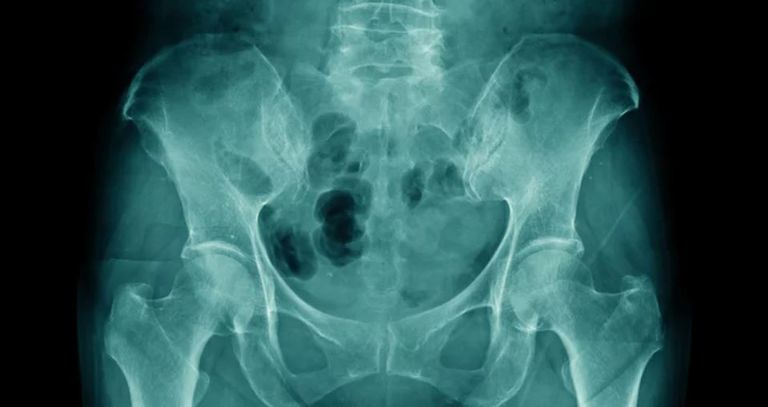

كانت ميلينديز تبلغ من العمر 92 عامًا عندما زارت الطبيب، وأثناء فحصها، أجرى الطبيب أشعة سينية كشفت عن وجود جنين متكلس في بطنها. وكشفت التحقيقات الإضافية أن الجنين كان يزن 4.4 رطلاً، وفقًا لصحيفة واشنطن بوست.

على عكس معظم المناظير الحجرية، لم يكن طفل ميلينديز الحجري موجودًا في بطنها ولكن في رحمها.

ما يقرب من 10٪ من جميع العمليات الحجرية تموت بالفعل وتتكلس في الرحم، وفي هذه الحالات، يستحيل على الأم أن تحمل مرة أخرى، وبالفعل، ليس لدى ميلينديز أي أطفال. على الرغم من صعوبة تحديد تاريخ عملية التكلس بالضبط، إلا أنها لا تقل عن 50 عامًا، وفقًا لـ CBS News .

غالبا ما يتم علاج هذه الحالات من خلال الاستئصال الجراحي، إلا أنه في هذه الحالة لم يتم إزالته بسبب كبر سن السيدة.